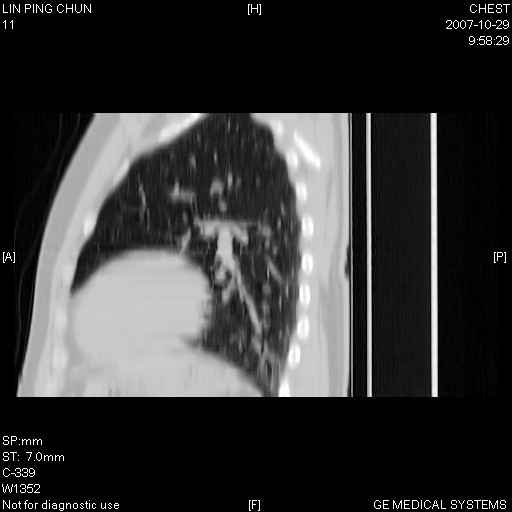

谢谢大家!!!上传纵隔窗,请大家帮我分析。

左下肺后基底段磨玻璃样影,很多病都可以。不能吊以轻心。应该做局部增强hrct进一步检查,并严格抗炎治疗后复查或经皮活检。

左下肺后基底段小斑片泪膜玻璃样影,其内可见空泡影,边缘可见小毛刺影。建议抗炎治疗复查,肿瘤待排

老兄,我建议您把病灶做个薄层处理,靶重建,然后上传过来,您仔细看看现在的病灶特点,小病灶,边界清,内见空泡征,高度警惕细支气管肺泡癌,最好的结局就是aah(不典型性腺瘤样增生).我会密切关注您的.另外,现在您可正规抗炎治疗半月后,与3个月后复查观察病灶变化,如没有太大变化,我建议您立即手术,放心!即使是肺癌也是早期,不会影响您的生命的,祝您好运.